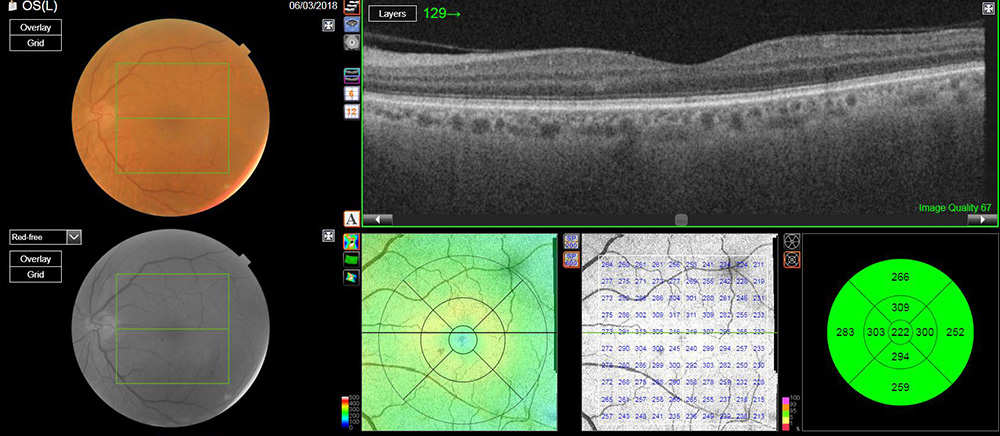

L’OCT (tomographie en cohérence optique) permet d’explorer en détail et en coupe les couches de tissu constituant la rétine, un peu comme un scanner. Cet examen permet notamment de mesurer l’épaisseur de la rétine afin de suivre son atrophie dans le temps, et d’observer les modifications structurelles des couches rétiniennes afin de caractériser les lésions maculaires. C’est un examen nécessaire pour distinguer les différentes formes de DMLA avant d’envisager un traitement ou une angiographie.

OCT d’une rétine normale

OCT montrant un décollement de l’épithélium pigmentaire et un décollement séreux rétinien typique d’une DMLA